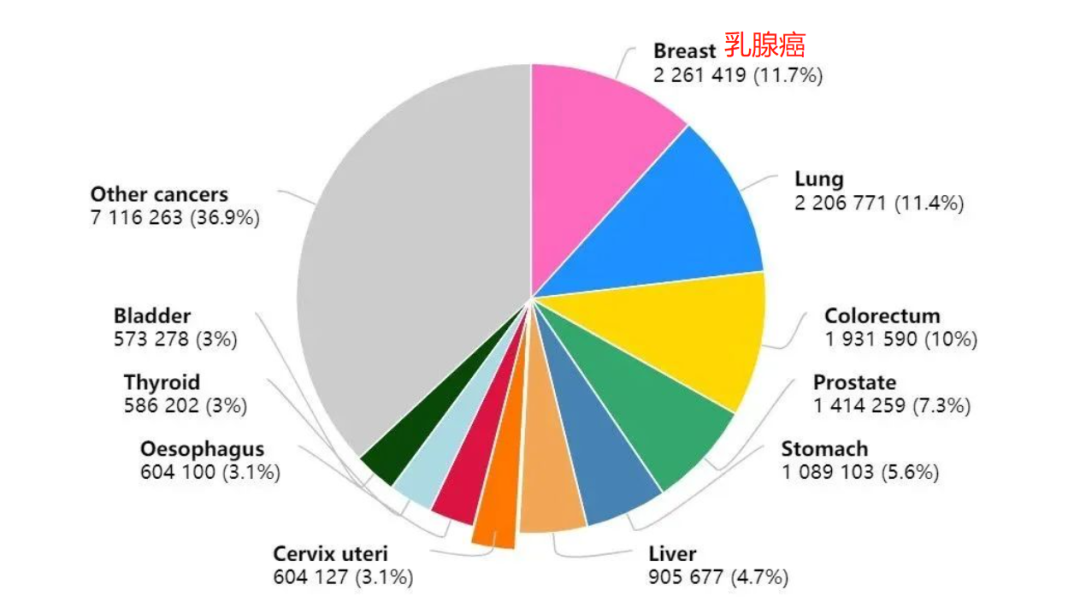

同时,乳腺癌发病率

也是所有癌症中最高的 ▼